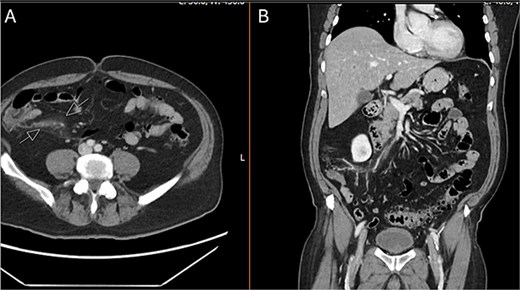

Upon arrival to the emergency department, the patient was hemodynamically stable and afebrile. On exam, the patient’s abdomen was soft, mildly distended, and tender in the right lower quadrant. He was noted to have a white blood cell count to 22.1, hemoglobin/hematocrit of 14.3/46.0, and platelets of 187. He had a lactic acidosis to 2.8. His electrolytes were unremarkable. CT scan of the abdomen and pelvis revealed no free air or free fluid, small amount of cecal wall thickening, and mild infiltrative changes within the mesenteric fat in the right lower quadrant with associated small mesenteric nodes with a normal-appearing appendix (Fig. 1).

CT abdomen and pelvis with IV contrast. A) Axial and B) coronal series identifying normal appendix and right lower quadrant mesenteric inflammatory changes.